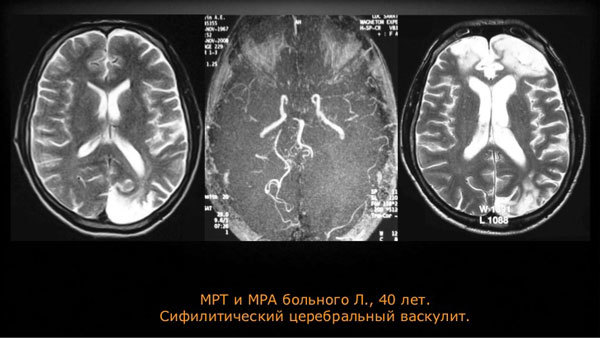

- Для идентификации артериитов головного мозга проводят МРТ и ангиографию. Для вен нижних конечностей показана допплерометрия.

Если у больного развилось поражение сосудов головного мозга, ему необходимо обратиться к специалисту. Невропатолог проведет опрос об особенностях проявлений болезни и осмотрит пациента. Затем доктор отметит отличительные характеристики от других заболеваний центральной нервной системы и направит на специальные методики диагностики. К ним относятся:

- ангиография сосудов мозга;

- УЗИ;

- МРТ;

- Ангиография с контрастированием;

- КТ;

- УЗ исследование с применением дуплексного сканирования церебрального кровотока.